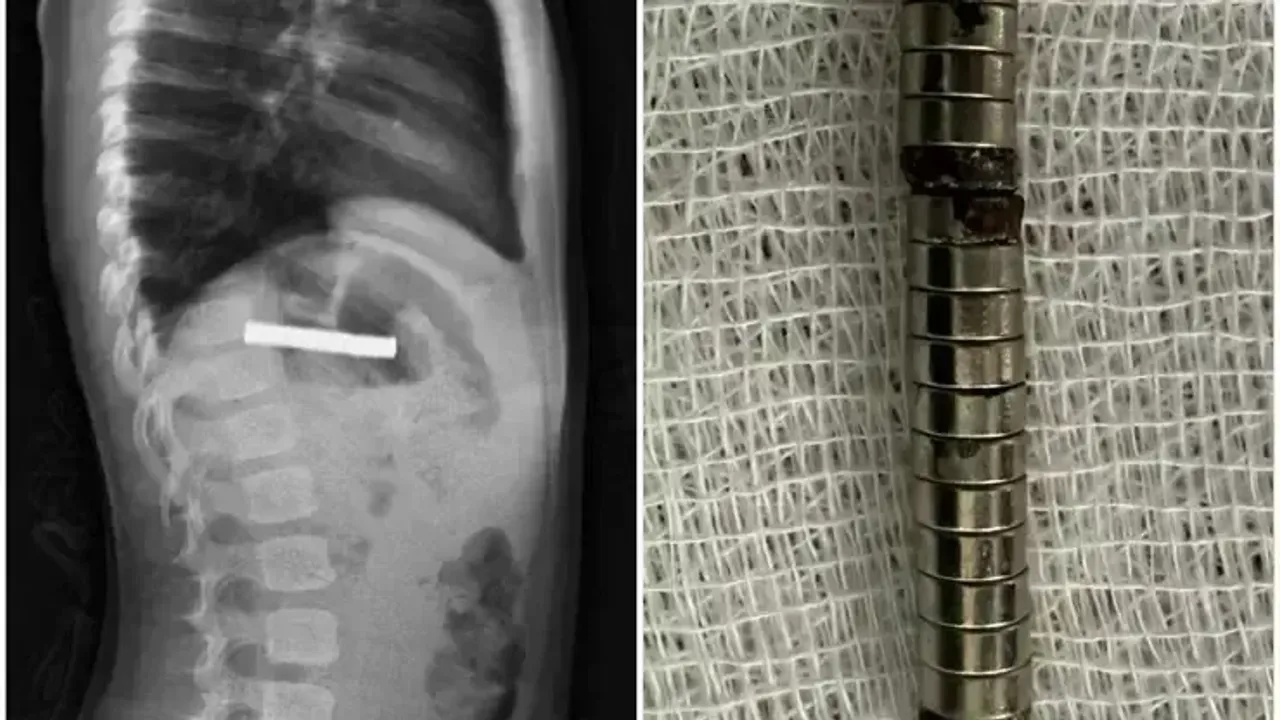

Fırat Üniversitesi Çocuk Gastroenteroloji, Hepatoloji ve Beslenme Bilim Dalı Başkanı Prof. Dr. Yaşar Doğan ve ekibi tarafından yapılan endoskopik operasyonla, mıknatıslar yemek borusundan mideye alınarak özel bir file yardımıyla çıkarıldı.

“Mıknatıslar çok güçlüydü. İşlemin kolay yapılabilmesi için onları mideye aldık ve özel bir fileyle çıkardık. Hastamızı gece boyunca gözlem altında tuttuk, genel durumu iyi olduğu için ertesi sabah taburcu ettik.”